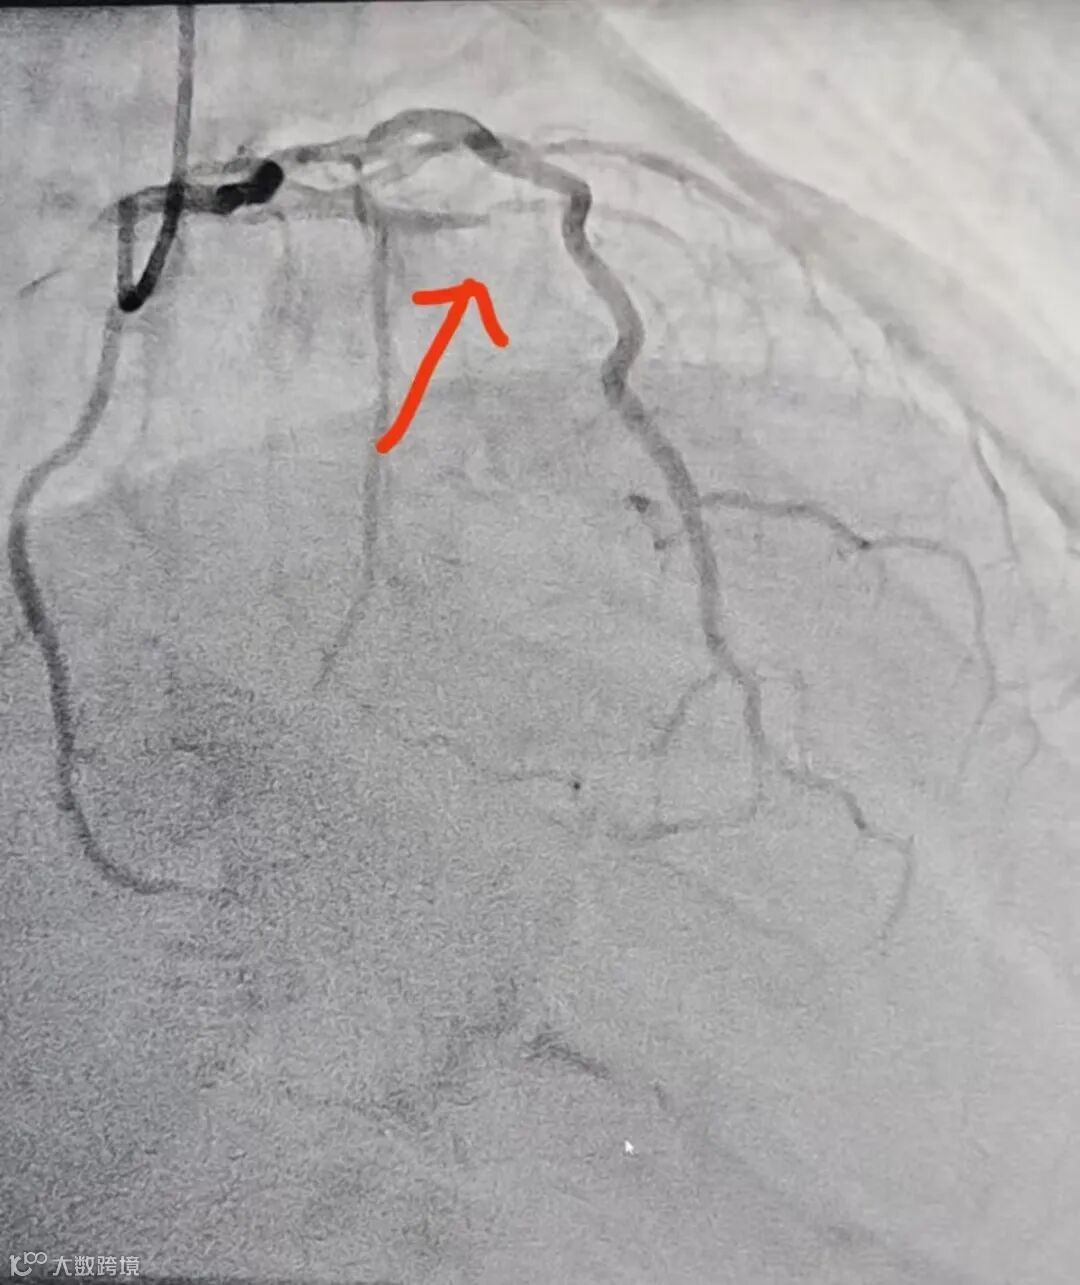

(球囊扩张与溶栓后血管通畅)